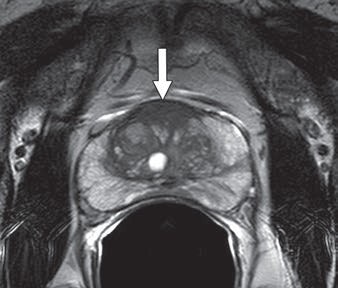

MR images are from a 65-year-old man with increasing prostate-specific antigen (PSA) level of 6.7 ng/mL and negative findings on TRUS-guided biopsy performed two years earlier. An axial T2-weighted MR image (above) shows nonencapsulated homogeneous triangular 1.9-cm focus (arrow) of reduced T2 signal in midline anterior transition zone. Axial oblique T2-weighted MR image (below) acquired in plane of needle introducer after needle deployment during direct MRI-guided biopsy shows needle (arrows) traversing target. Images courtesy of AJR."The present study supports the use of direct MRI-guided biopsy as an appropriate problem-solving diagnostic approach for patients with suspicious findings on MRI and negative findings of prior TRUS-guided systematic biopsy, biopsy-naive patients, or patients with a prior biopsy showing Gleason score 6 disease only," Meermeier and colleagues concluded. "As such, we would suggest that direct MRI-guided biopsy be considered in those scenarios for patients who may otherwise be considered for TRUS-guided systematic biopsy or saturation biopsy."